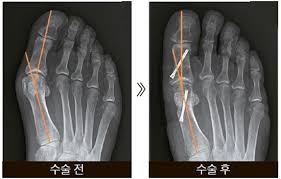

또한, 복합 골절이나 압박 골절과 같이 더 복잡한 경우에는 수술이 필요할 수 있으며, 뼈가 조각나거나 비스듬하게 부러진 경우에는 금속판을 추가적으로 사용할 수 있습니다.

- 뼈가 사선으로 부러진 경우: 이 경우 깁스만으로는 충분한 고정이 되지 않으므로 수술이 필요할 수 있습니다.